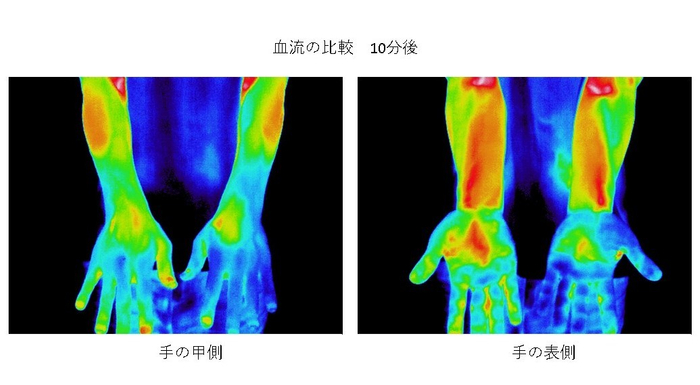

血流促進・温暖効果

「コロバニィ」に使用している素材はラジウムなどの鉱石類とオーガニック炭が含まれています。

これらの原料は微量ながらも非常に高い遠赤外線輻射熱をもち、シリカ含有率の高いオーガニック炭がもたらす輻射熱とラジウムなどの温泉鉱石により、広範囲の血流を促進します。実験を重ねた結果この効果を認められ、この素材を使用した製品が一般医療機器として登録されており、コロバニィも登録準備を進めています。

図2 温度の変化

図2は両手の“甲”に数センチ角の加工済布片を貼って10分後の様子。左手はただの布ですが、右手は加工した布を貼っています。明らかに右手の血流が促進されているのがわかります。